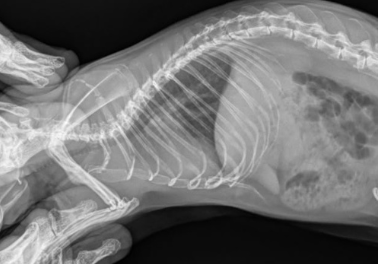

Поехали снимать швы, по итогу и это отложилось из-за дыхания крысы. Отправили на рентген. Сделали. Сначала говорили, что по тени сердца кажется, что увеличено. Потом откинули вариант, сказали, что газы в желудке, так как хватает ртом воздух.

Сердце на рг увеличено, выражен лёгочный рисунок. По УЗИ ничего не могу сказать.

Я думаю да. В лёгких ничего страшного нет, желудок не раздут (он мог бы выдавать дыхание ртом) а газы в кишечнике незначительные. Нос синеет, одышка есть, дыхание ртом есть. Сердце в любом случае перекачивается.

Воспаление в носу на рентгене , не исключено, что это связано с глазом, что то его выдавливало же. Для доп диагностики нужно кт.

Не очень, понимаю что там с сердцем нормально, на боковой проекции оно приличных таких размеров.